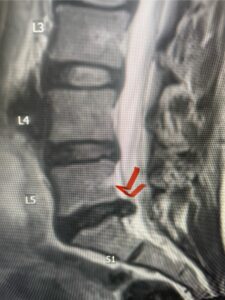

Figures 1a: Sagittal and axial T2-weighted lumbar MRIs demonstrating a grade 1 L2-3 spondylolisthesis (red arrow) with severe stenosis secondary to right L2-3 facet hypertrophy (red arrow).

In this next case, this patient is a 47 year-old female who presents with intractable low back pain with severe pain, numbness, and weakness in the right lower extremity that had gotten progressively worse over a year. The patient had failed conservative management including physical therapy and epidurals. She was noted to have ⅘ weakness of plantar flexion. MRI demonstrated a large right L5-S1 disc herniation with severe compression of the descending right S1 nerve root (Fig 3). It was decided to perform a right L5-S1 hemilaminectomy for removal of the disc fragment and decompress the S1 nerve root. When you expose the disc, one must be certain to release any anterior adhesions to the nerve root in order to prevent a dural tear during retraction of the nerve root. It is also important to make sure during exposure and you finally encounter the dura after removing the ligamentum and fat, to make sure you are looking at the nerve root and not the main trunk of the thecal sac because if you don’t you can avulse or damage the nerve root if you retract the wrong structure.

Fig. 3a: Sagittal and axial T2-weighted lumbar MRI images demonstrating large right L5-S1 disc herniation (red arrows)

We found a massive subligamentous herniation which had to be revealed by having your partner retract the freed nerve root with a nerve root retractor and putting slight downward pressure on the more medial and anterior disc space. There is nothing more satisfying when the jelly (disc fragment) of the annulus (donut) comes squirting out and you remove a large chunk of disc material that clearly was stretching the ligament membrane and compressing the nerve root. This does cause back pain in addition to radiculopathy not only by the component of mechanical compression but also the stretching of the nerves within the ligament. We performed this surgery and noted that the nerve root was a very angry red color or hyperemic and we removed a large subligamentous fragment. The patient had improvement of her preoperative radicular symptoms.